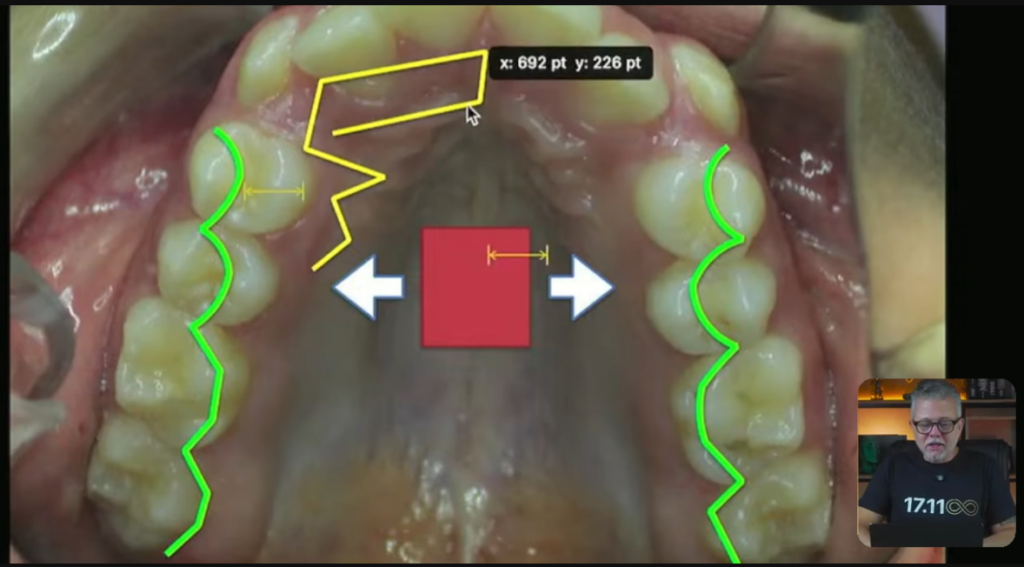

Então, esse verdinho que você está vendo aqui, ele vai fazer esse tipo de movimento:

Esses pré vão expandir desse jeito que você acabou de ver. Muito mais na região dos pré do que dos molares, tá?

Vai acontecer uma expansão nessa região.

E na ortopedia, a gente também coloca um negócio chamado mola frontal. Ela encosta no lateral e ela leva esse lateralzinho para vestibular:

Eu posso muito bem pegar o diagrama ortodôntico do meu paciente e fazer com que esse diagrama fique mais ou menos com esse formato:

Professor, mas eu posso fazer esse formato de arco no meu paciente que parece um formato de arco um pouco mais quadrado, expansivo, só no fio, assim, só no formato do fio?

Claro que você pode, desde que o corredor bucal da paciente permita um pouco de expansão na região dos prés.

Ah, então quer dizer que aqui eu não precisaria nem de quadriélice, nem de disjuntor, nem de expansor. Eu conseguiria fazer tudo isso com o formato do fio?